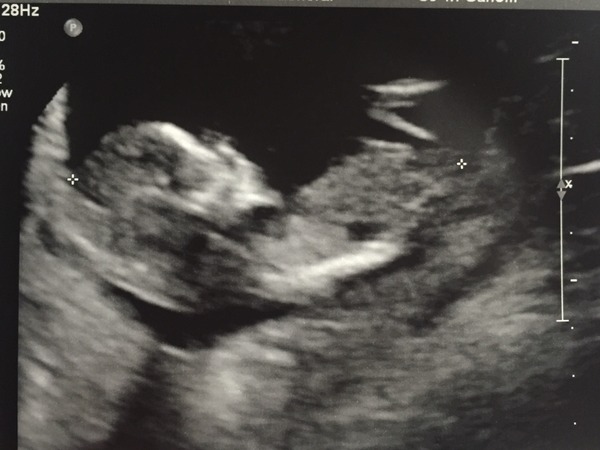

Checking in, I'm allegedly 12+6 based on LMP but I was having 32 day cycles so I'm more like 12+2. I tried to explain this at my midwife appointment but it was like 'computer says no' and my due date was confirmed on my file based on LMP, most frustrating. My scan didn't match either date so it's all a bit mind boggling.